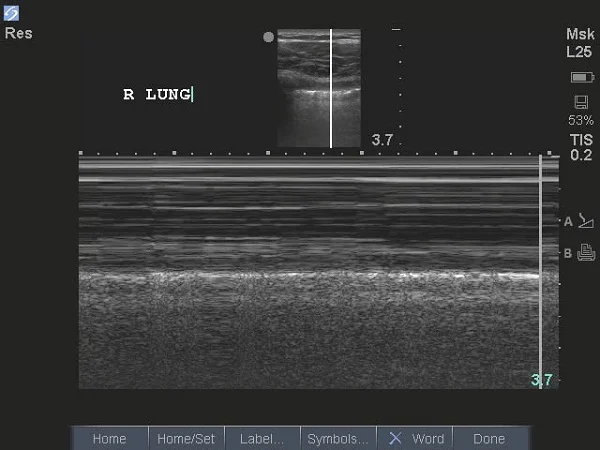

- You can confirm lung sliding with M-Mode and you should visualize the “seashore sign” as above

- The “sand” of the “seashore sign” is produced by haphazard reflection of the sound waves in multiple different directions off of the spherical alveoli

- If an area of no lung sliding is found, you can use M-mode to confirm which will not show the typical “seashore sign” but will show the “stratosphere sign”